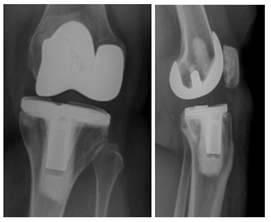

A 52-year-old woman underwent a left total knee arthroplasty 7-years prior with a cemented CR Zimmer® NexGen® total knee system (Zimmer-Biomet, Warsaw, IN) secondary to rheumatoid arthritis. She had a history of rheumatoid arthritis, lymphoma, COPD, deep vein thrombosis as well as obesity (5’5”, 226Lbs, BMI 37). She presented for follow up 5-years after her original surgery with symptoms of pain, difficulty ambulating, and an audible clunk. She demonstrated abnormal AP mechanics with significant anterior tibia translation. She was noted to have near complete wear through the posterior medial corner of her polyethylene (Figure 1) and was subsequently revised to 14mm AC polyethylene with resolution of her abnormal mechanics (Figure 2).

Figure 1 AP/Lateral left knee 5years from TKA with medial joint space narrowing and anterior translation of the tibia.

Figure 2 AP/Lateral left knee, status post revision TKA to a 14mm AC constrained polyethylene with resolution of joint space asymmetry and appropriate alignment on the lateral view.